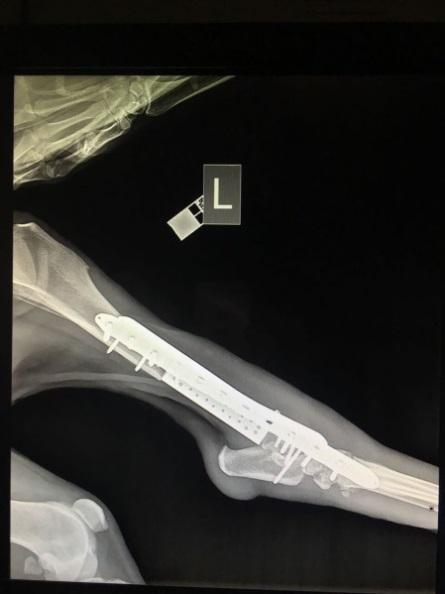

Рис. 2 — Рентгеновский снимок задней конечности животного после установки имплантата.